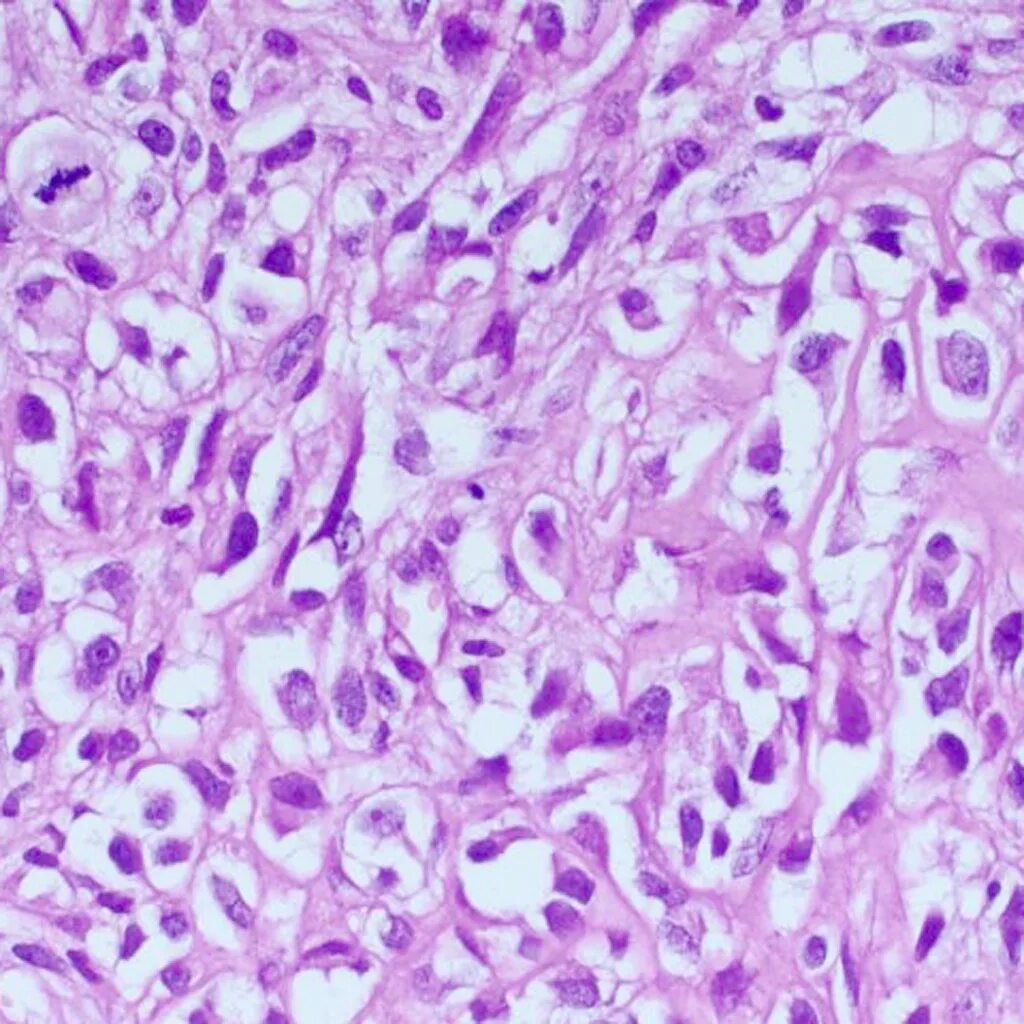

Гистология челюстей